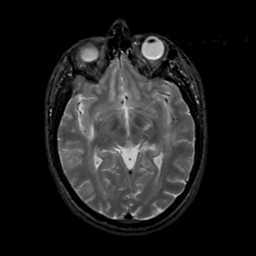

MR Study #20 October 6, 1991 -- Slice #23

[Home][Help][Clinical][Tour 1][Tour 2] Slice 23